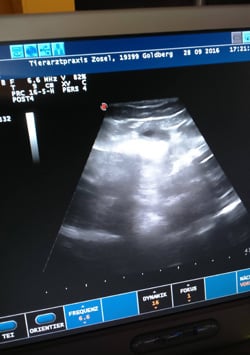

28.09.2016 Juhuu .... wir sind schwanger!

Heute hatte ich mit Cassi einen Ultraschalltermin und es hat sich bestätigt, dass sie aufgenommen hat! Wir erwarten unseren Nachwuchs Anfang November.

Och ist das alles Aufregend!